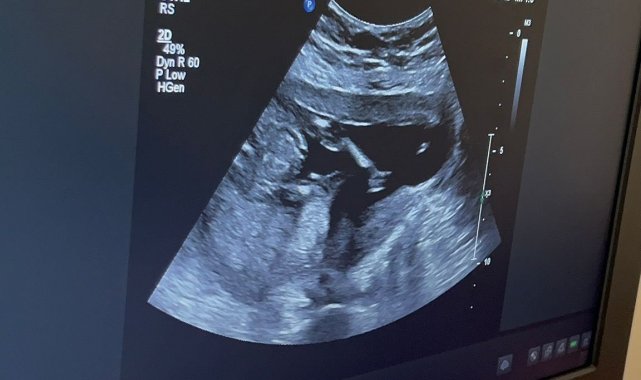

Kütahya Şehir Hastanesi'nde Amniyosentez hizmeti başladı

Kütahya Şehir Hastanesi'nde, Kadın Hastalıkları ve Doğum Uzmanı, Perinatoloji (Riskli Gebelik) Yan Dal Uzmanı Uzm. Dr. Fatih Akkuş'un atanmasıyla birlikte, amniyosentez işlemi uygulanmaya başlandı.